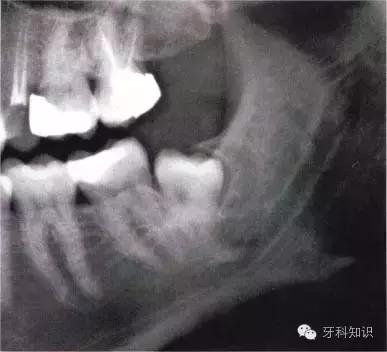

全颌曲面断层×线片。切割牙冠时应经过阻生牙远中面的牙颈部的釉牙骨质交界处

下颌升支前缘的骨吸收区有利于牙片的取出